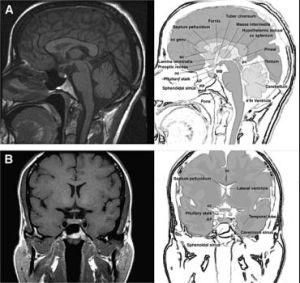

臨床表現為視力視野障礙,影像學檢查可見鞍區病變,蝶鞍骨質變化。如有內分泌表現診斷一般不難,需和顱咽管瘤、腦膜瘤、動脈瘤等鑑別,MRI對發現微腺瘤很有意義。

垂體瘤診斷方面,影像學檢查是非常重要的手段。其中以鞍區的核磁共振(MRI)檢查對垂體瘤的檢出率最高。通過鞍區薄層(每1mm掃描一層)增強影像的MRI檢測,若結合動態造影MRI檢測,直徑小至2-3mm的垂體微腺瘤也可以顯像。鞍區增強CT顯像對於部分垂體大腺瘤顯像效果好,可以了解鞍底骨質的破壞程度以及蝶竇氣化的程度。